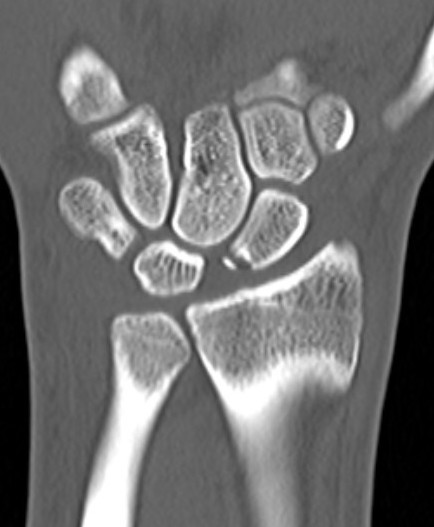

X-ray

Scapholunate gap > 3 mm

AP

| Terry Thomas sign | Cortical ring sign | Scaphoid shortened |

|---|---|---|

|

Increased scapholunate interval > 3 mm compared with other side |

End on view of distal scaphoid due to flexion | Shortened due to flexion |